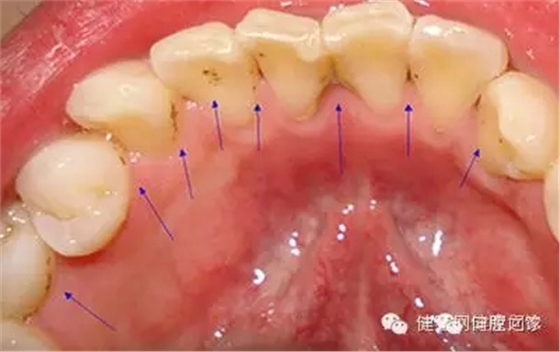

牙垢也叫牙菌斑,是附著在牙齦冠部、頸部及牙縫間的污垢。牙垢主要是食物殘渣、口腔黏膜脫落的上皮、唾液及細菌混合而成。牙垢久積,容易鈣化成牙結(jié)石。牙垢沉積的多少、快慢,因人而異,與口腔衛(wèi)生習慣、食物成分、咀嚼習慣、牙齒排列及機體代謝情況有關(guān),最快可形成于潔牙后的48小時。 牙垢可能造成哪些危害?

1. 形成蛀牙。牙垢中的細菌常見如鏈球菌、厭氧菌、葡萄球菌等,牙垢形成一定厚度后,緊挨壓面的細菌在無氧呼吸作用下會加快腐蝕牙石表面的礦物質(zhì),產(chǎn)生蛀牙問題。

2. 牙周疾病。牙垢久積,容易形成牙結(jié)石,牙石的存在會妨礙口腔衛(wèi)生,促使菌斑更多地形成,牙石本身也會吸附更多的細菌和毒素,造成牙齦充血、水腫,產(chǎn)生牙齦炎、牙周炎等問題;